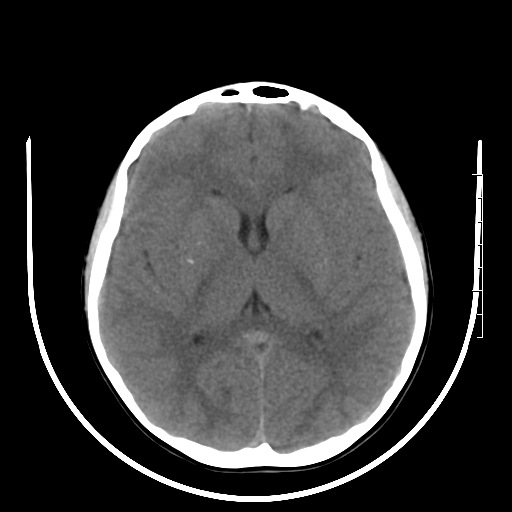

标题: PED3377:m、9y,恶心、呕吐,每月发作2-3次。 [打印本页]

标题: PED3377:m、9y,恶心、呕吐,每月发作2-3次。

颅脑ct轴位平扫颅内未见明确异常。

右侧壳核多枚点状钙化灶。去请结合临床。

右侧壳核多枚点状钙化灶,请结合临床。

右侧壳核多发钙化灶,请结合临床。